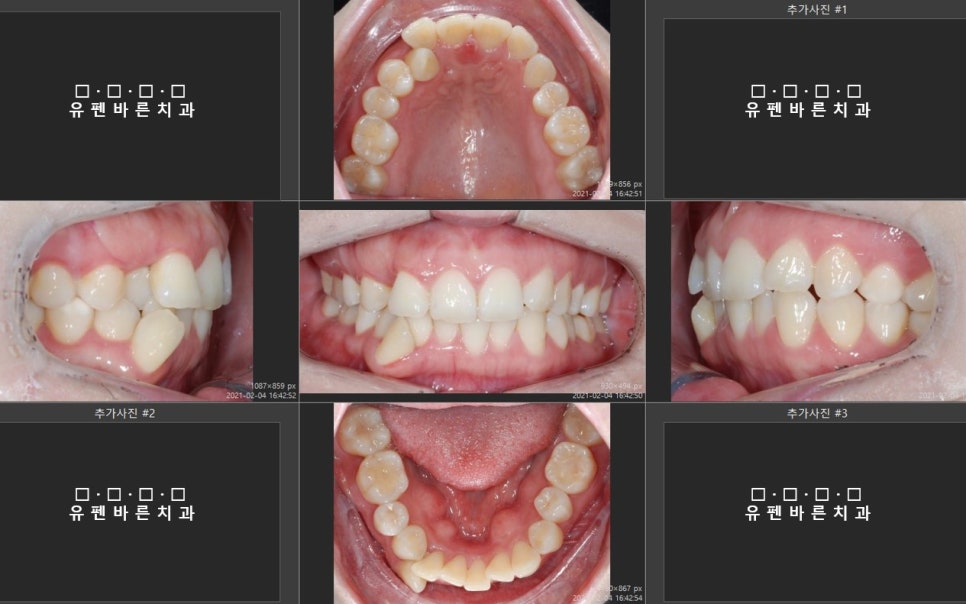

이 환자분은

삐뚤빼뚤한 치아와

오른쪽 위아래

덧니 해결을 위해

내원하셨어요.

현재

영국에 거주중 이셔서

잠시 한국에 계시는 동안

인비절라인을 시작하기로 하셨습니다.